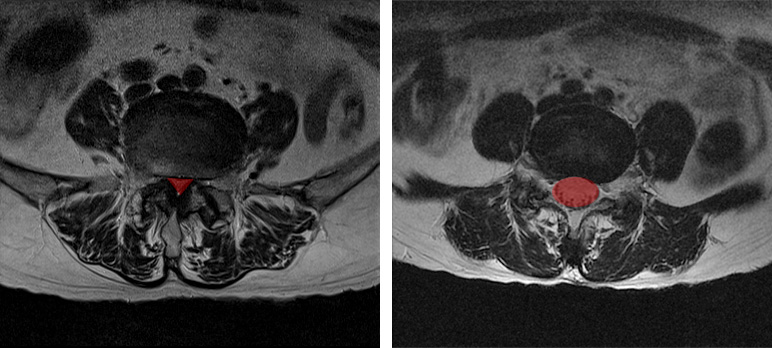

첫 번째 경우는 X-ray나 MRI 검사결과를 보고 디스크의 높이가 낮아진 것을 협착이라고 착각하는 경우입니다. 디스크가 퇴행되었거나 또는 디스크가 탈출되어 수핵이 빠져나가면 디스크의 높이가 낮아지는데, 디스크의 높이가 낮아지면 '디스크가 눌려서 압착되어 있으니까 이게 협착이구나' 하고 착각하게 되는 것 같습니다. 사실 협착이라는 단어는 일상생활에서 잘 쓰지 않는 단어이기 때문에 눌려서 압착되어 있는 걸 협착이라고 오해하는 것이죠. 그러나 디스크에 퇴행성 변화가 발생하여 디스크의 높이가 낮아진 것은 협착이 아니라, 그냥 허리디스크입니다. 협착이라는 것은 디스크를 옆에서 봤을 때 디스크가 눌린 게 아니고, 척추관이 좁아진 것을 말합니다.

척추관이 좁아지게 되면 MRI로도 많이 좁아진 게 보이며, 반대로 협착증이 아닌 경우에는 MRI 상으로도 공간이 넓습니다. 따라서 단순히 디스크의 높이가 낮아진 것을 보고 이걸 협착이라고 착각하시면 안 됩니다.

협착의 정확한 뜻은 어떤 관이나 구멍, 또는 이와 유사한 구조물들의 안쪽 폭이 좁아진 상태를 뜻합니다. 그래서 사전적인 의미로만 본다면, 당연히 디스크만 밀려나와도 척추관 구멍의 넓이는 좁아집니다. 그러나 이렇게 디스크가 밀려나와서 척추관이 좁아졌다고 해도 이것을 협착증이라고 진단할 수 있는 것은 아닙니다. 디스크가 밀려나온 것은 그냥 허리디스크지, 협착증이 아닙니다. 한 10년 전만 하더라도 이렇게 밀려나온 디스크로 척추관이 좁아지면, 좁아진다는 의미로써 narrowing이라는 단어를 많이 썼는데, 최근 몇 년 사이 좁아졌다는 표현보다는 '협착'이란 단어를 의사들이 훨씬 더 많이 써서 표현하고 있습니다. 이렇듯 의료진들이 디스크 때문에 척추관이 좁아졌다는 의미로 협착이란 단어를 쓰면, 환자들은 '아 내가 협착증이구나' 하고 오해하게 됩니다. 따라서 디스크가 밀려나와서 척추관이 좁아졌다는 의미로 협착이란 말을 진료 시에 쓰는 것은 바람직한 현상이 아니라고 저희는 생각하고 있습니다. 왜냐하면 허리디스크인 환자가 협착증이라고 잘못 오해하게 되면, 협착증에 맞지 않는 잘못된 운동을 할 수 있고, 또한 잘못된 치료로 이어질 수 있기 때문입니다. 예를 들면 저희는 협착증 환자분들에게는 맥켄지 운동을 하지 말라고 말씀 드리는데, 간혹 본인은 맥켄지 운동을 하니까 좋은 것 같다고 말하는 경우가 있습니다. 이런 분들은 협착증 진단이 제대로 되었는지 확인할 필요가 있습니다. 협착증 환자가 맥켄지 운동을 하면 안 되는 이유에 대한 자세한 내용은 아래 영상을 보시길 바랍니다.

그러다 보니 허리를 숙인 상태에서 쇼핑카트를 밀면서 걸으면 통증이 좀 나아지는데, 이 때문에 외국에서는 협착증 환자의 이런 증상을 Shopping Cart Sign이라고 부르기도 합니다. 이 간헐적 신경 파행 증상이 협착증에 동반되는 이유는 협착증은 디스크만의 문제가 아니라 뼈, 후관절, 척추관 내 인대, 디스크 등 모든 척추구조물이 다 퇴행된 상태이기 때문입니다. 그래서 증상이 아주 복합적으로 나오는 것이죠. 따라서 MRI상으로 척추관이 좁아진 것이 보임과 동시에 반드시 간헐적 신경성 파행 증상까지 나타나야만 진정한 의미의 협착증임을 알아두시길 바랍니다.